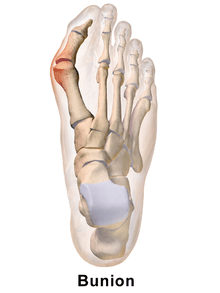

Bunion

A bunion is a deformity of the joint connecting the big toe to the foot. It is characterized by medial deviation of the first metatarsal bone and lateral deviation of the hallux (big toe), often erroneously described as an enlargement of bone or tissue around the joint at the bottom of the big toe (known as the metatarsophalangeal joint).

The bump itself is partly due to the swollen bursal sac or an osseous (bony) anomaly on the metatarsophalangeal joint. The larger part of the bump is a normal part of the head of the first metatarsal bone that has tilted sideways to stick out at its distal (far) end.

Bunions are commonly associated with a deviated position of the big toe toward the second toe, and the deviation in the angle between the first and second metatarsal bones of the foot. The small sesamoid bones found beneath the first metatarsal (which help the flexor tendon bend the big toe downwards) may also become deviated over time as the first metatarsal bone drifts away from its normal position. Arthritis of the big toe joint, diminished and/or altered range of motion, and discomfort with pressure applied to the bump or with motion of the joint, may all accompany bunion development. Atop of the first metatarsal head either medially or dorso-medially, there can also arise a bursa that when inflamed (bursitis), can be the most painful aspect of the process.